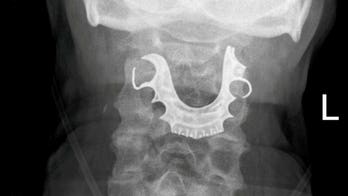

DENTAL HEALTH August 12, 2019 Man undergoes emergency surgery after dentures found lodged in throat days following procedure A 72-year-old man’s dentures were found lodged in his throat eight days after he had surgery, leading to complications and forcing him to later undergo an emergency procedure.Â